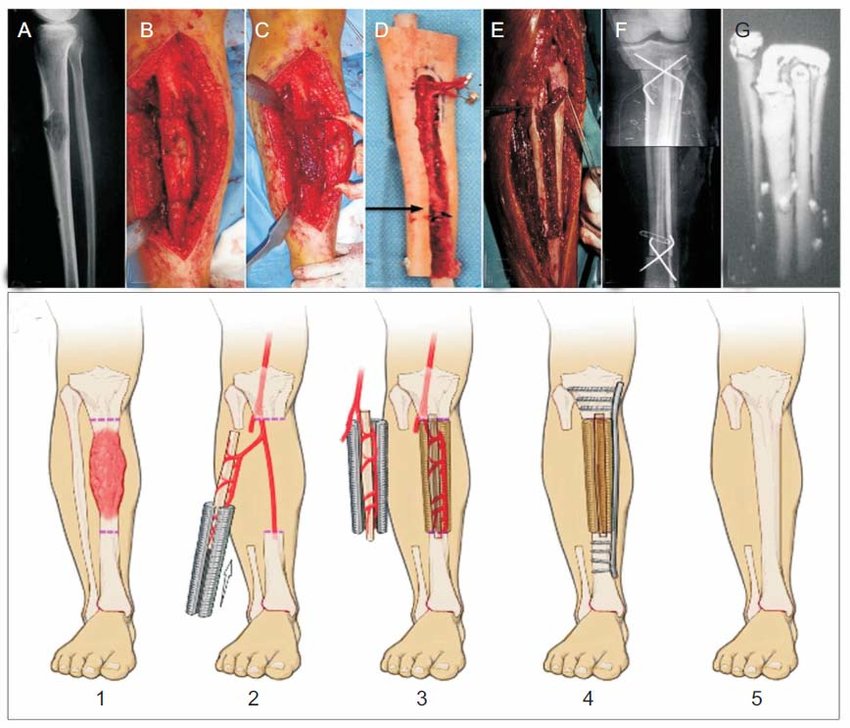

최근에는 동종골 이식 뼈 기술이 많이 발전하긴 했지만, 자가골 이식의 골생성이나 유합정도를 이기기는 힘듭니다. 주로 이식을 위한 뼈는 경골, 비골, 장골 에서 채취하게 됩니다. 아무래도 이러한 뼈 채취부위의 특징은 회복이 빠르고, 구조적인 장점을 가지며 골생성 능력도 좋은 부분 입니다.

3. 비골